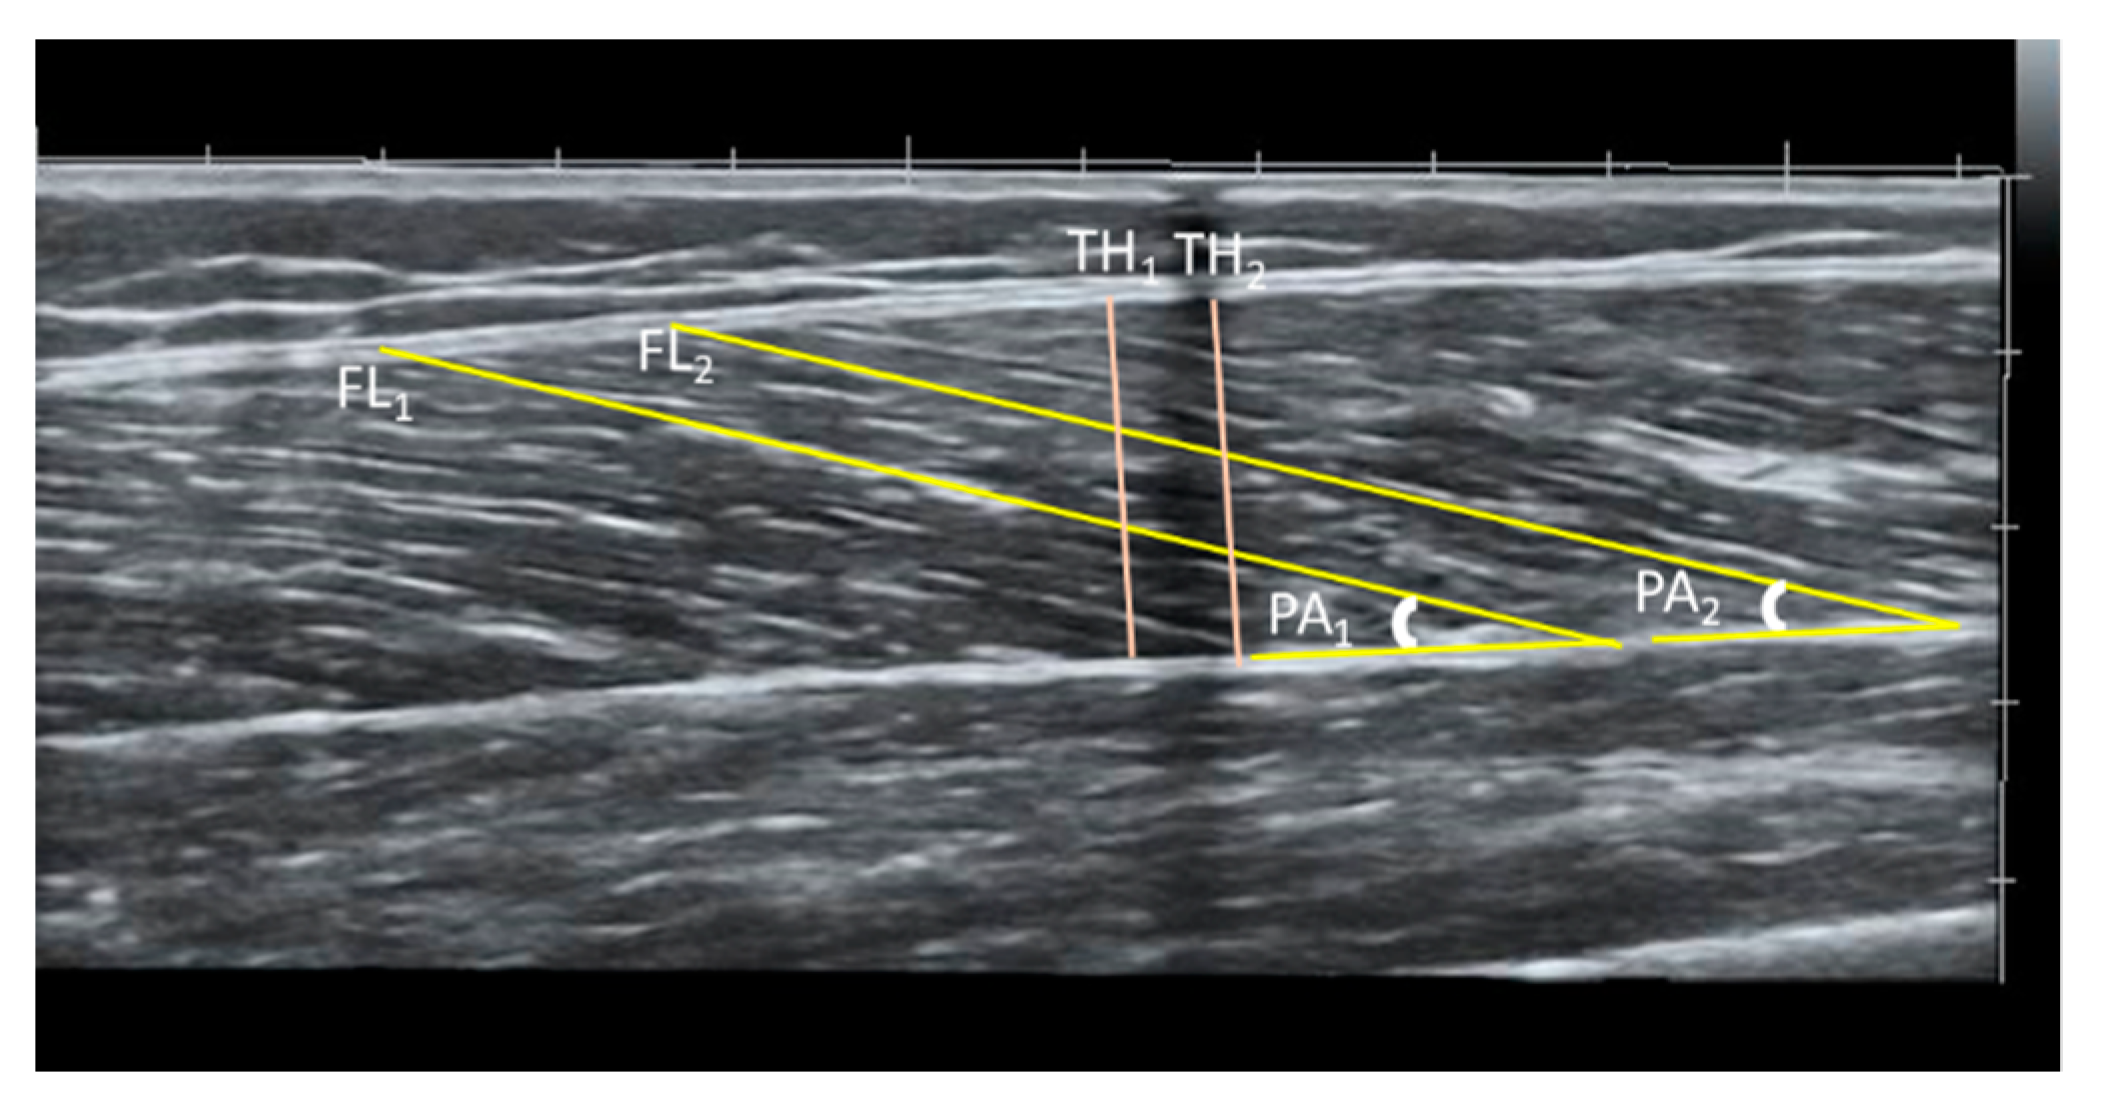

2.3.2. Muscle Architecture and Ultrasound

| Fascicle length (m) | 0.077 | 0.007 |

| Pennation angle (ο) | 15.528 | 1.435 |

| Thickness (m) | 0.020 | 0.002 |